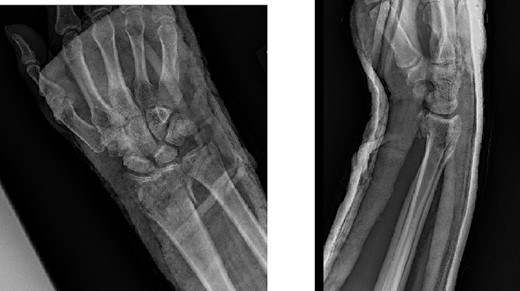

A dorsal spanning plate was planned to treat the fracture. An incision was made over the third dorsal compartment followed by release of the fourth dorsal compartment to fully visualize the fracture. Once the plate was placed, intraoperative fluoroscopy revealed that that radial styloid was still displaced. After releasing the first dorsal compartment and brachioradialis, a radiostyloid plate was then placed. Additionally, the volar ulnar corner of the radius was still not reduced properly, so a Protean fragment specific volar buttress plate was placed. Final intraoperative fluoroscopy films revealed satisfactory reduction and alignment (Figs 3 and 4).

Two weeks following the procedure, the patient returned to the clinic for a follow-up visit. The wrist was swollen and ROM was limited. Hand motor functions and neurovascular exam were fully intact. Radiographs taken in clinic showed intact hardware with healing fracture. At 2 months follow-up, radiographs showed intact hardware with interval bone bridging across fracture sites. Radiographic parameters including articular alignment, radial height, radial inclination, and volar tilt were in acceptable ranges (Fig. 5). The patient reported no concerns or complications. A computed tomography (CT) scan was obtained at 10 weeks after the procedure and confirmed adequate bony healing and alignment without failure (Fig. 6). The dorsal spanning plate was eventually removed 1 month later and 4 months since the initial operation (Fig. 7).

Radiological assessment at 2 months postprocedure with PA and lateral views.